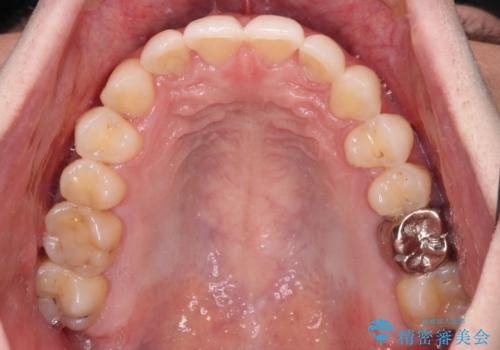

ディープバイトと叢生 インビザラインによる矯正治療

- 前歯のディープバイトと叢生を気にして来院された患者様です。

上下ともに叢生が認められたため、親知らずすべてを抜歯し、歯列全体を後方へ移動させることで歯列を整えることとしました。

上顎奥歯の銀歯も気になっていたので、矯正治療の途中でセラミッククラウンへ変更し、その後歯列を仕上げていくこととしました。

ディープバイトもデコボコも改善され、気になっていた銀歯もセラミックとなり、患者様には大変満足していただきました。